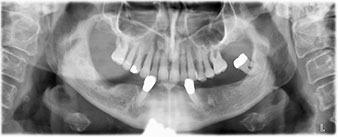

La paciente de 64 años se presentó con una dentición residual compuesta por las piezas dentales 38, 33 y 43 en el maxilar inferior y con una prótesis temporal fijada con ganchos en el maxilar inferior (figs. 1 y 2).

dentición residual

Fig. 1

Fig. 2